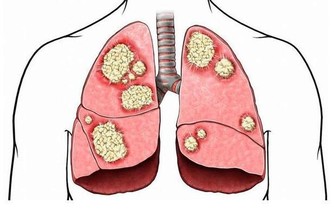

病毒感染在人體中間是非常普遍的。例如,在不發達國家,幾乎所有的成年人都感染了單純皰疹病毒;而幾乎每個人也都患有上呼吸道感染這樣的疾病。人體內的病毒感染大多為隱性感染。絕大多數顯性感染的病毒感染都是急性感染,發病時間短,病程短,大多在1 至2 週內自行痊癒。還有少數病毒感染通過潛伏感染和慢性感染表現出相應症狀。

多數研究結果顯示,某些病毒感染與腫瘤的發生密切相關,如與EB病毒感染有關的鼻咽癌,與乙型肝炎病毒感染有關的原發性肝癌,以及與子宮頸癌有關的相關癌症。呼吸道、消化道、皮膚粘膜、眼睛等器官都是病毒感染的渠道。感染病毒的兒童比成人多。輕微病毒感染患者可以不需要外界干預也可以康復,嚴重感染的患者會遭受死亡威脅和殘留後遺症。